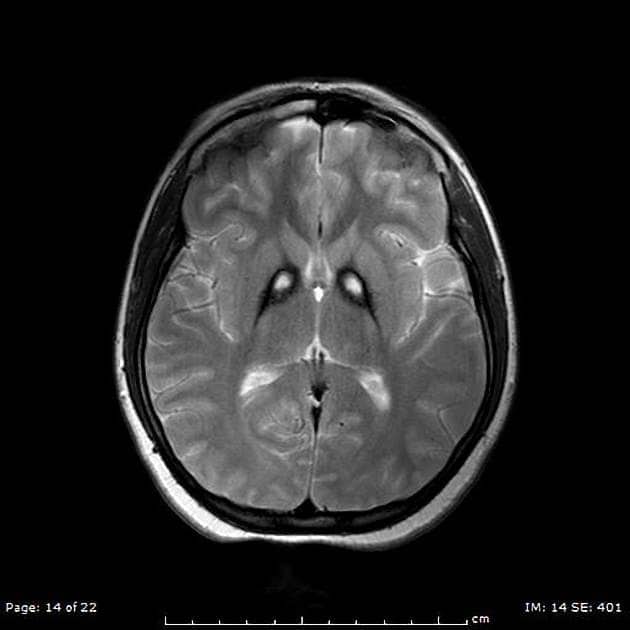

PKAN Disease: Exploring Symptoms, Genetic Causes, and Progression

Classic PKAN: Understanding Early Onset Symptoms and Progression

PKAN & Dystonia: Navigating Involuntary Muscle Contractions